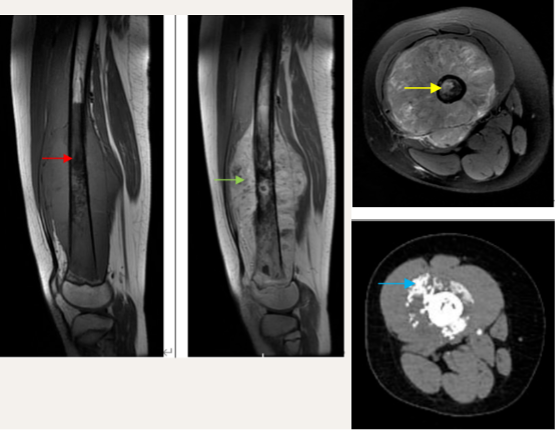

骨肉瘤在MRI图像上呈现T1加权低信号(红箭头),T2加权等高信号(黄箭头),软组织肿块呈现弥漫性增强(绿箭头)。新辅助化疗后软组织肿块显著缩小,钙化明显(蓝箭头)。